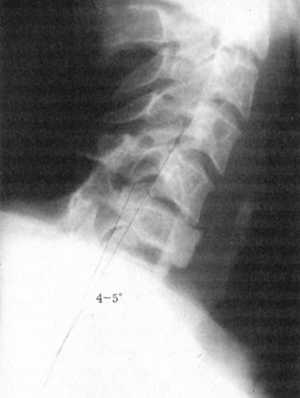

При компрессии спинного мозга передними структурами в шейном отделе позвоночника,

блоке субарахноидального пространства, определяемых рентгенологическими, радиоизотопными

и МРТ-исследованиями, выполняется передняя декомпрессия спинного мозга с межтеловым

спондилодезом. Разрез кожи по передней поверхности шеи осуществляется на неоперированной

стороне (у оперированных больных) по медиальному краю грудино-ключично-сосцевидной

мышцы (m. sternocleidomastoideus) или поперечно над проекцией повреждения.

Используется пара-трахеальный доступ к месту поражения - передней поверхности

поврежденного позвонка (позвонков). Удаляется тело позвонка вместе с выше-

и нижнерасположенными дисками, освобождается дуральный мешок от компримирующих

тканей и оценивается внешний вид твердой мозговой оболочки (ТМО): ее целостность,

подвижность и пульсация. При отсутствии пульсации, напряжении ТМО последняя

вскрывается Z-образно, осматривается спинной мозг, восстанавливается ликвороциркуляция.

ТМО закрывается, при необходимости проводится ее пластика. Проводится межтеловой

спондилодез, гемостаз. Целесообразно активное дренирование раны в течение

суток. Рана ушивается послойно. Накладывается ватно-марлевый воротник типа

Шанца (рис. 12.2, 12.3). Для нейропротекции целесообразно перед операцией

ввести разово бо-люсно метилпреднизолон (солюмедрол) из расчета 30 мг/кг и

продолжать его введение в течение 2 сут по схеме как при острой травме, особенно

у больных с признаками сохраненной функции СМ.

Рис. 12.2. Застарелый осложненный вывих

С6 позвонка |

Рис. 12.3. Рентгенограмма после хирургического

лечения |